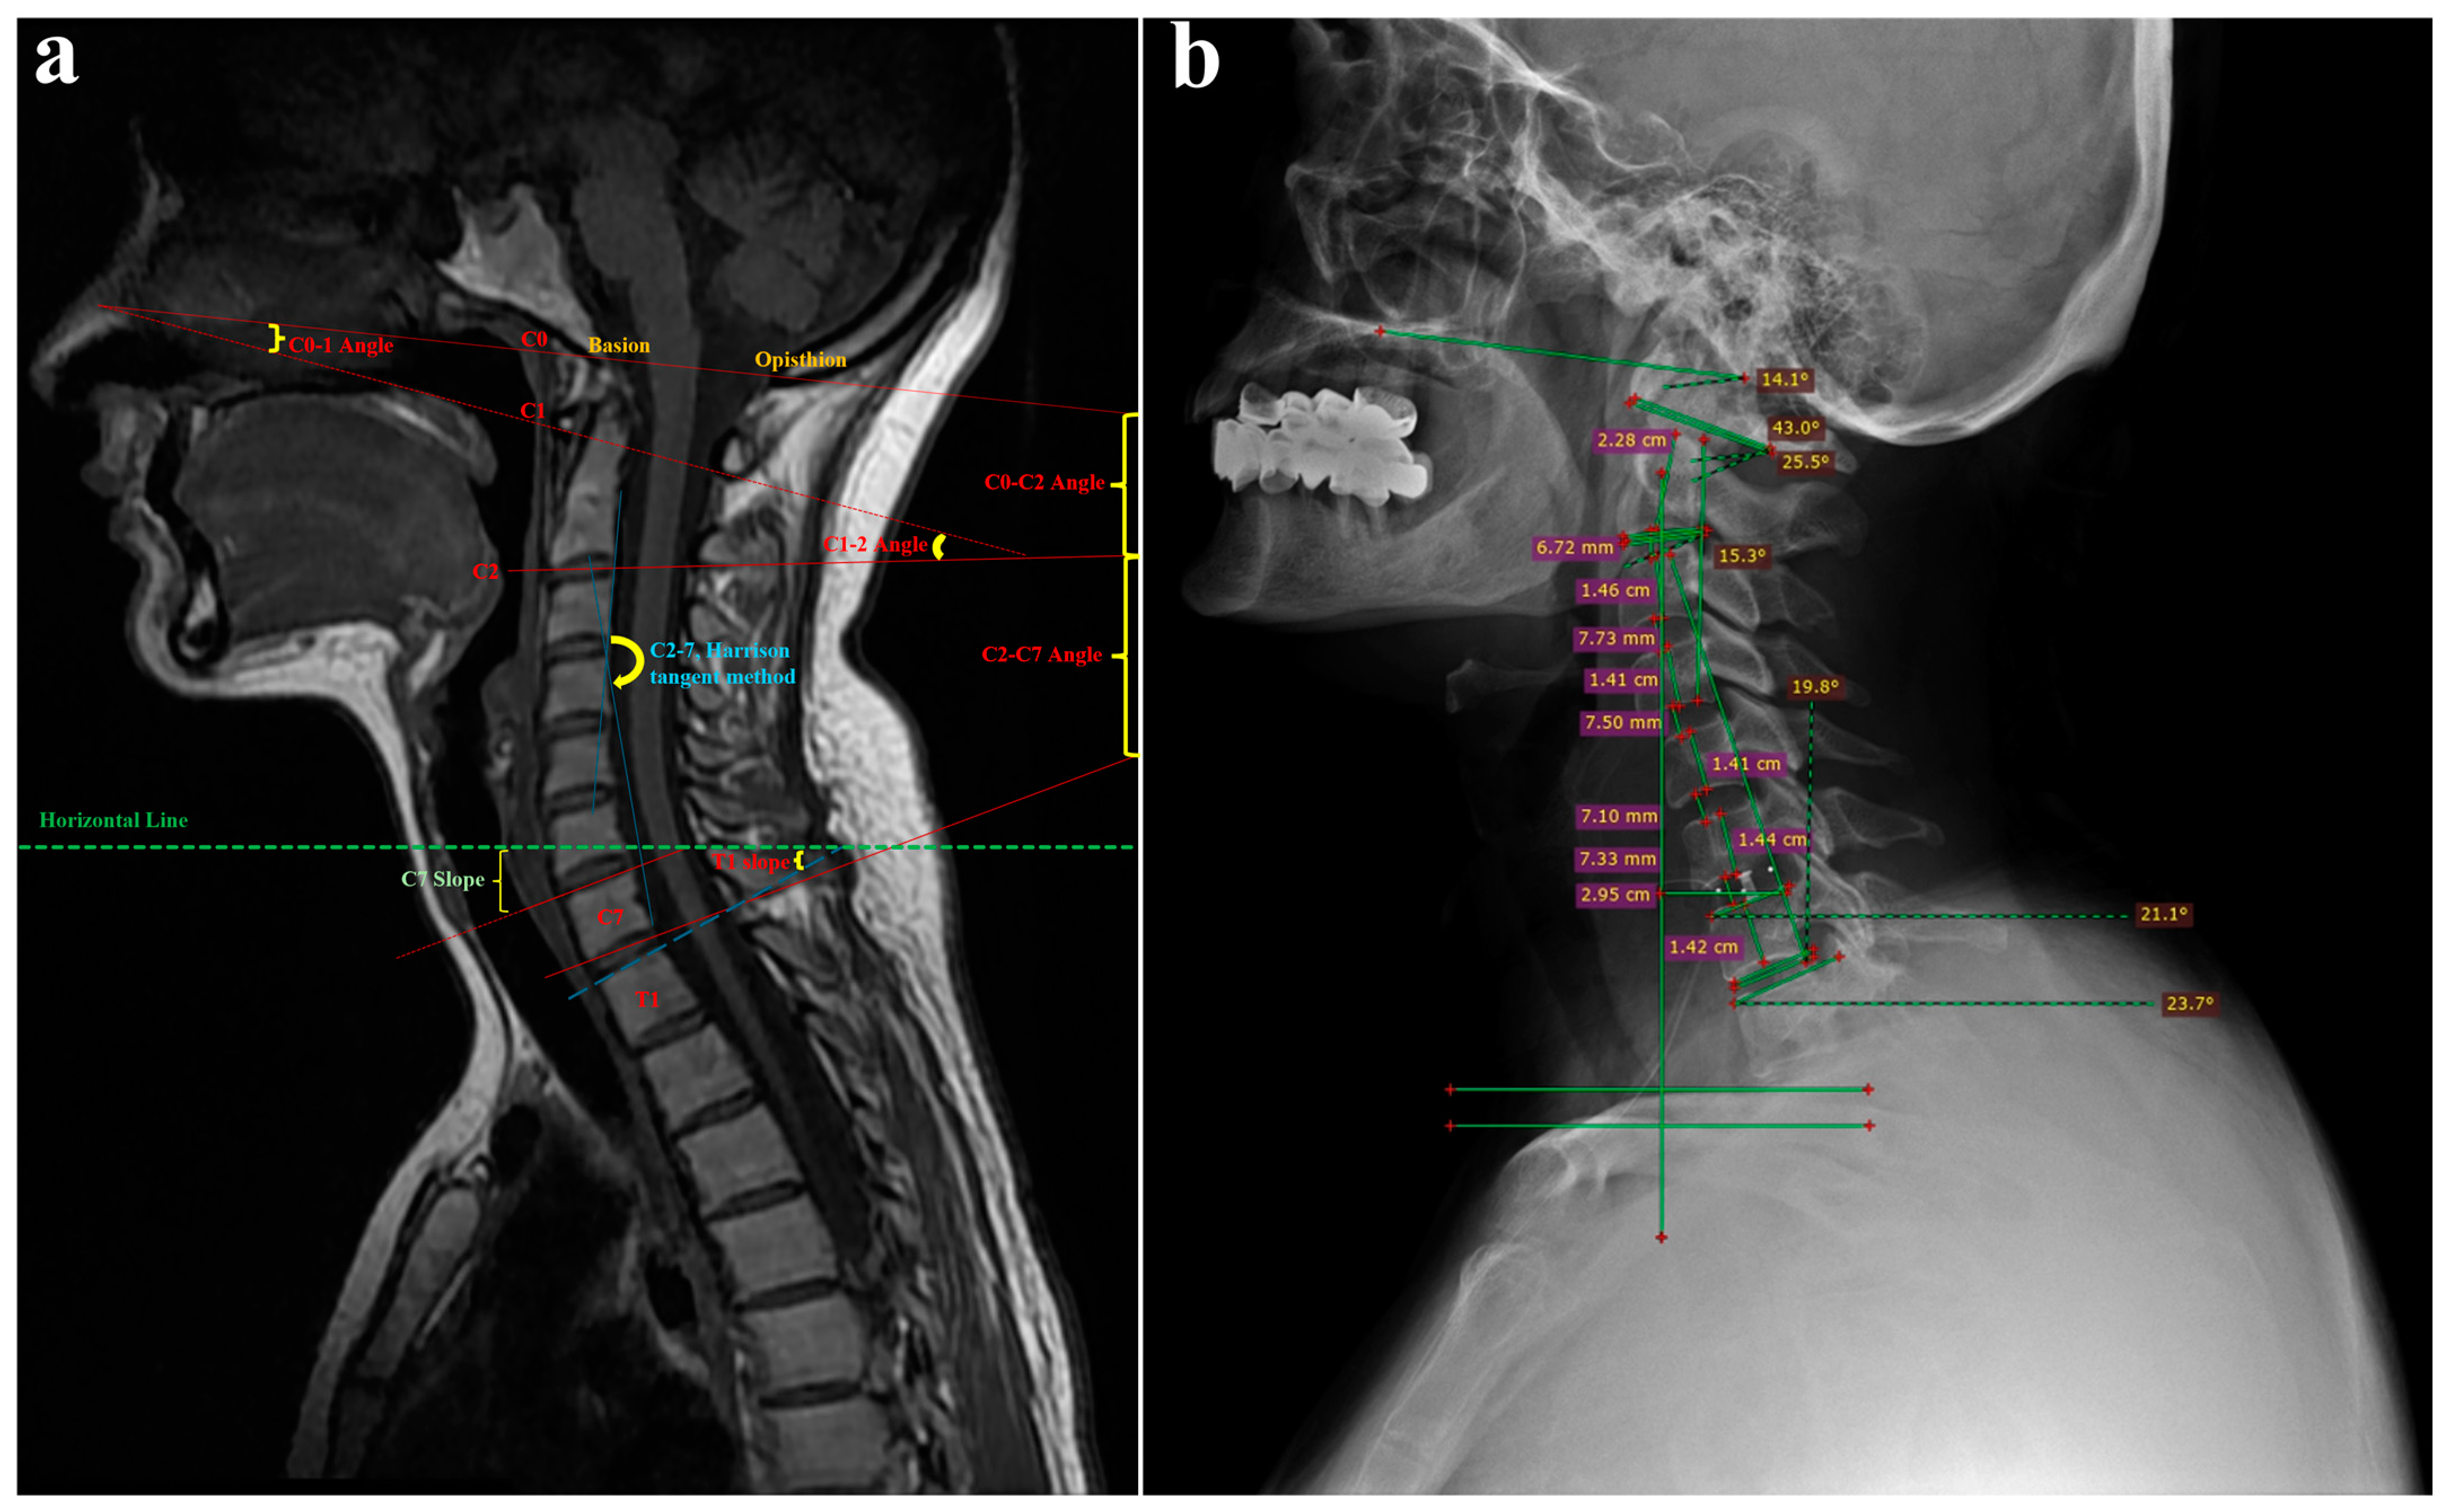

2.2. Radiological Assessment

2.5. Clinical and Radiological Assessment